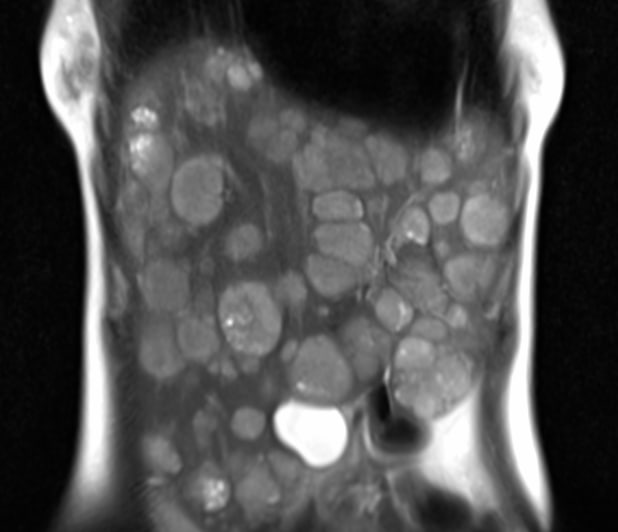

Одно из самых паскудных проявлений злокачественной опухоли - перитонеальный карциноматоз.

Средняя выживаемость при нем по одним данным составляет от 2,3 до 9 месяцев, по другим - варьирует от 11 до 17 месяцев при первичной опухоли, и зависит от стадии первичной опухоли при вторичном (стадии 0-2 - 5-10 месяцев, стадии 3-4 - 2-3,9 месяцев). Расположение первичной опухоли также может влиять на показатели выживаемости: при колоректальной карциноме средняя продолжительность жизни составляет 6,9 месяцев. Средняя продолжительность жизни при опухоли желудка составляет 6,5 месяцев.

Девушка 72 лет с карциноматозом брюшины, известно, что была гистерэктомия, а при перитонеальном карциноматозе, вызванном раком эндометрия средняя продолжительность жизни не превышает 12 месяцев, хотя при проведении циторедуктивной хирургии в сочетании с гипертермической внутрибрюшинной терапии описывают случаи продолжительности жизни и до 3 лет (интересно, что саудиты такое опубликовали, можно ли верить? Хотя, французы опубликовали, что после такого лечения аж трое пациентов прожили 7, 23 и 39 месяцев).

А у вас в местечке проводят такую терапию?